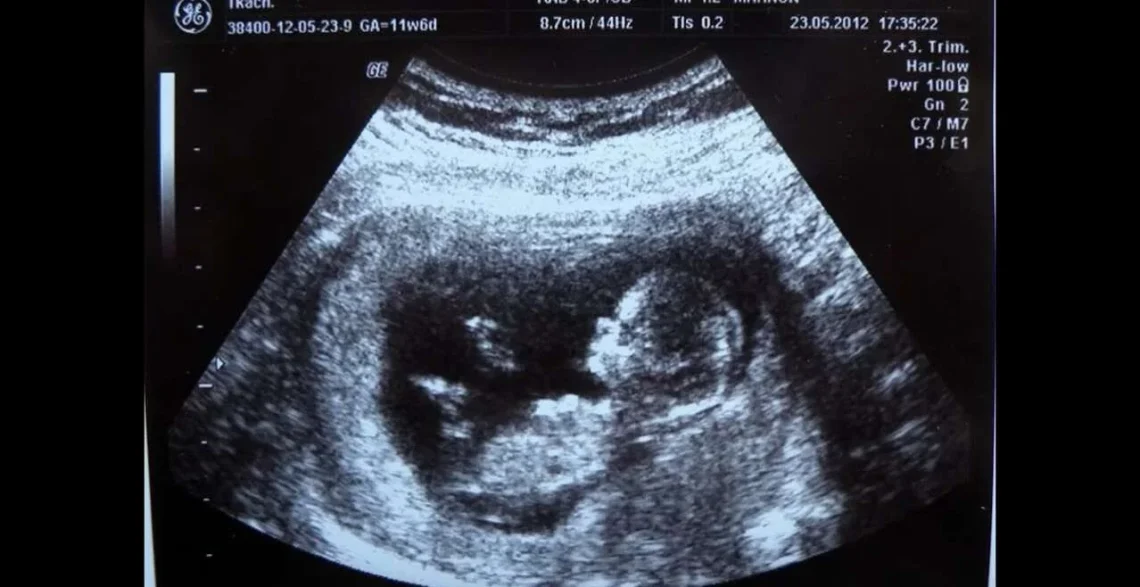

حذّر باحثون من جامعة أوبسالا في السويد من أن الأطفال الذين يُولدون لأمهات تجاوزن سن الـ45 معرضون بشكل أكبر لمخاطر صحية عند الولادة، مقارنة بأبناء الأمهات الأصغر سناً.

ومع تقدم النساء في السن، لا سيّما بعد الأربعين، تزداد احتمالات حدوث مضاعفات أثناء الحمل والولادة. ويعود ذلك إلى التغيرات الطبيعية في الجسم، مثل انخفاض جودة البويضات، وزيادة خطر الإصابة بمشكلات صحية مزمنة، مثل ارتفاع ضغط الدم والسكري، والتي قد تؤثر على صحة الحمل. كما ترتفع معدلات الإجهاض والولادة المبكرة، ويزداد احتمال اللجوء إلى الولادة القيصرية. إضافةً إلى ذلك، فإن استجابة الجسم للتغيرات الهرمونية تكون أبطأ؛ مما يجعل الحمل أكثر تطلباً من الناحية الطبية.

وأظهرت النتائج أن نسبة الولادات الميتة (وفاة الجنين داخل الرحم) بلغت 0.83 في المائة بين الأمهات فوق سن 45، مقارنة بـ0.42 في المائة فقط في الفئة العمرية 35 – 39 عاماً. كما لوحظ ارتفاع في نسب الولادة المبكرة من 4.8 في المائة في الفئة الأصغر إلى 8.4 في المائة لدى الأمهات الأكبر سناً. وتُشير النتائج إلى أن تقدّم عمر الأم يؤثر بشكل واضح على صحة المواليد، خصوصاً في الفئة التي تجاوزت سن الـ45.